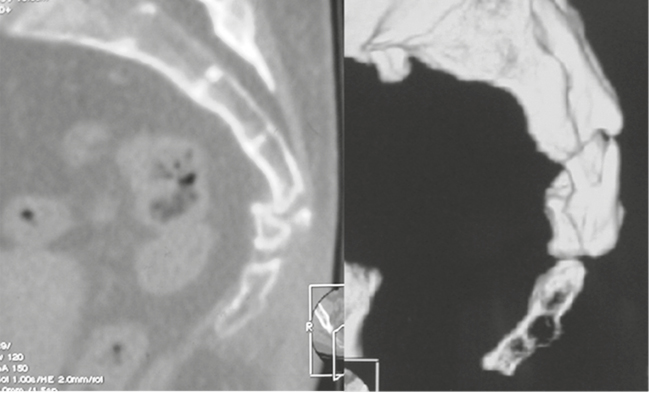

Второе клиническое наблюдение. Пациентка Б., 39 лет, находилась на лечении в клинике военной травматологии и ортопедии Военно-медицинской академии им. С.М. Кирова в июне 2019 г. Травму копчика получила 16 месяцев назад, катаясь на «ватрушке». Получала длительное консервативное лечение по поводу кокцигодинии (физиотерапия, анальгетики, блокады) с временным эффектом. По данным лучевого исследования выявлен застарелый подвывих копчика кзади и наличие костной «спикулы», спонтанный «костный блок» на уровне крестцово-копчикового сочленения (рис. 4). При ректальном исследовании обнаружена значительная подвижность копчика, сопровождающаяся выраженной болью. В клинике больной выполнена резекция копчика, послеоперационное течение без осложнений (рис. 5–8). Пациентка выписана на 4-е сутки после операции. Индекс ВАШ через 1 месяц после операции составил 2 балла, а при дальнейшем наблюдении — 1 балл. По шкале удовлетворенности операцией — «полностью удовлетворена».

Рис. 7. Вид операционной раны пациентки Б. после резекции копчика

Fig. 7. Intraoperative photograph of the patient B. after resection of coccyx

Рис.8. Рентгенография крестца и копчика пациентки Б. после операции

Fig. 8. X-ray of the sacrum and coccyx of patient B. after a surgery